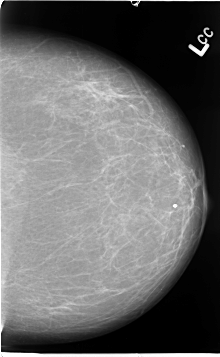

B_3067_1.LEFT_MLO

LEFT_MLO LINES 4656 PIXELS_PER_LINE 3136 BITS_PER_PIXEL 12 RESOLUTION 50 NON_OVERLAY